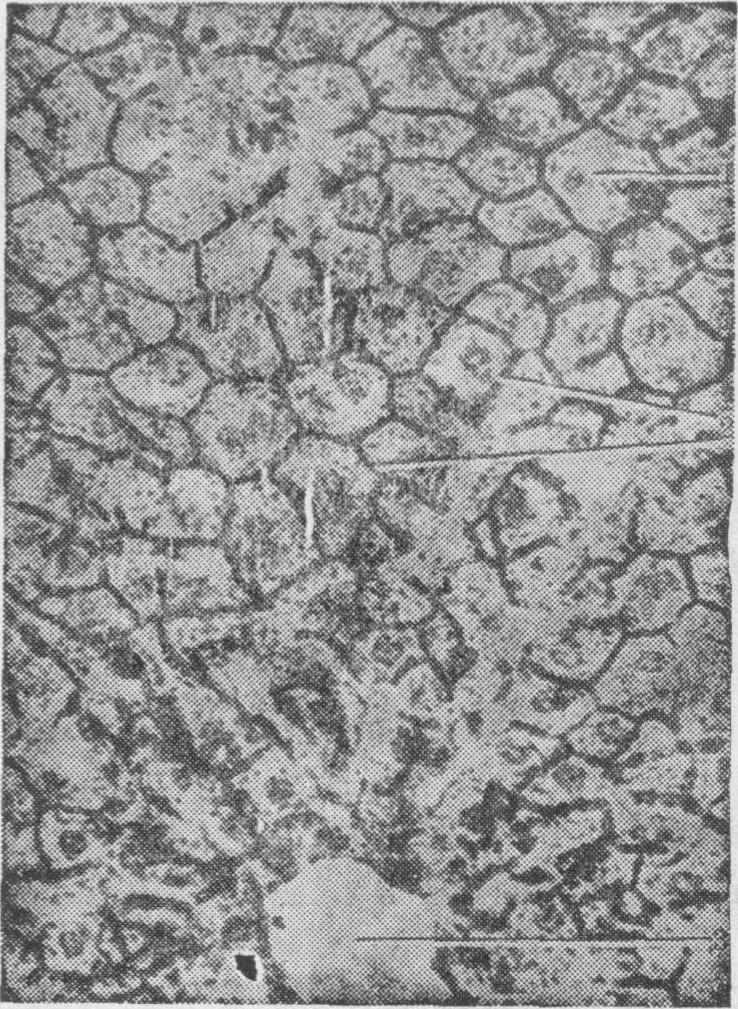

肝小叶 肝小叶是肝的结构和功能单位,由Kiernan(1833)提出,一直沿用至今,故又称经典肝小叶。肝小叶呈多角形棱柱体,长约2mm,宽约0.7mm,成人肝大约有100万个。每个肝小叶的中央有一条中央静脉贯穿其长轴,静脉周围是肝细胞组成的肝板和肝血窦(图1)。各小叶之间由结缔组织分隔。猪、猫等的小叶间结缔组织较发达,肝小叶分界清楚;人肝结缔组织较少,小叶分界不明显(图2)。

图2 肝小叶与门管区切面图

1.门管区 2.中央静脉 3.肝索 4.肝血窦5.小叶间结缔组织

肝板与肝索 肝板由单层肝细胞组成,是以中央静脉为中心呈放射状排列的细胞板。肝板曲折不平,相邻肝板常互相连接。肝板之间为肝血窦,血窦经肝板上的孔互相通连成网(图3)。在肝切片中肝板的断面称肝索(图4)。在肝小叶周边,肝板相互连接组成小叶边界性的界板。小叶周边的界板延续围绕在门管区周围。门管区血管的分支穿过界板,通连肝血窦。

图3 肝板与肝血窦立体模式图

1.中央静脉 2.肝板 3.肝血窦 4.小叶间动脉 5.小叶间静脉 6.小叶间胆管 7.Hering管 8.胆小管